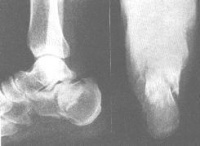

足跟可极度肿胀,踝后沟变浅,整个后足部肿胀压痛,易被误诊为扭伤。 X 线检查,除摄侧位片外,应拍跟骨轴位像,以确定骨折类型及严重程度。此外,跟骨属海绵质骨,压缩后常无清晰的骨折线,有时不易分辨,常须依据骨的外形改变,结节 - 关节角的测量,来分析骨折的严重程度。

(5)接近跟距关节的骨折 为跟骨体的骨折,损伤机制亦为高处跌下跟骨着地,或足跟受到从下面向上的反冲击力量而引起。骨折线为斜行。 X 线片正面看,骨折线由内后斜向前外,但不通过跟距关节面。因跟骨为骨松质,因此轴线位观,跟骨体两侧增宽;侧位像,跟骨体后一半连同跟骨结节向后上移位,使跟骨腹部向足心凸出成摇椅状。